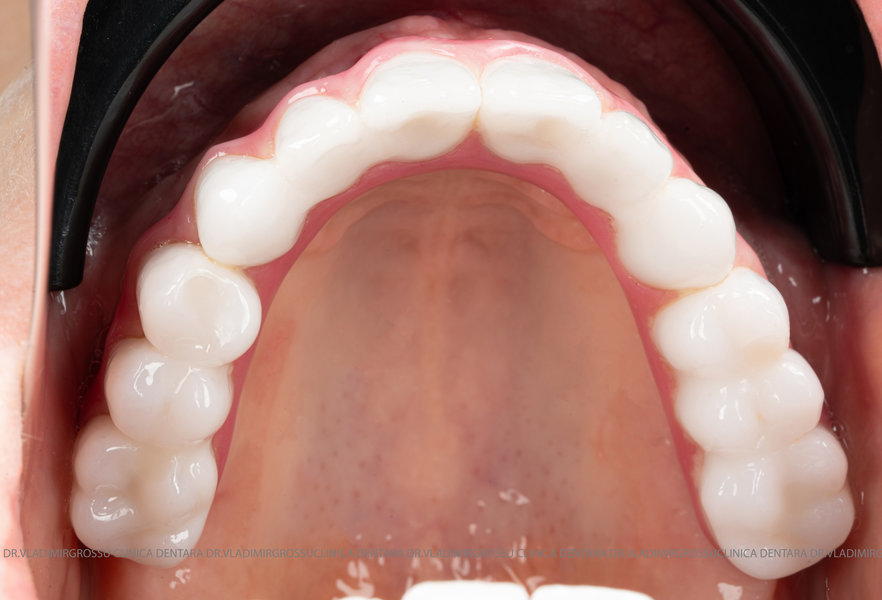

- Posibilitatea realizării unei proteze cu 12-14 dinți, oferind un aspect estetic natural și funcționalitate optimă.

- Proteză definitivă realizată din metaloceramică sau zirconiu, cu 12-14 unități (soluția recomandată).